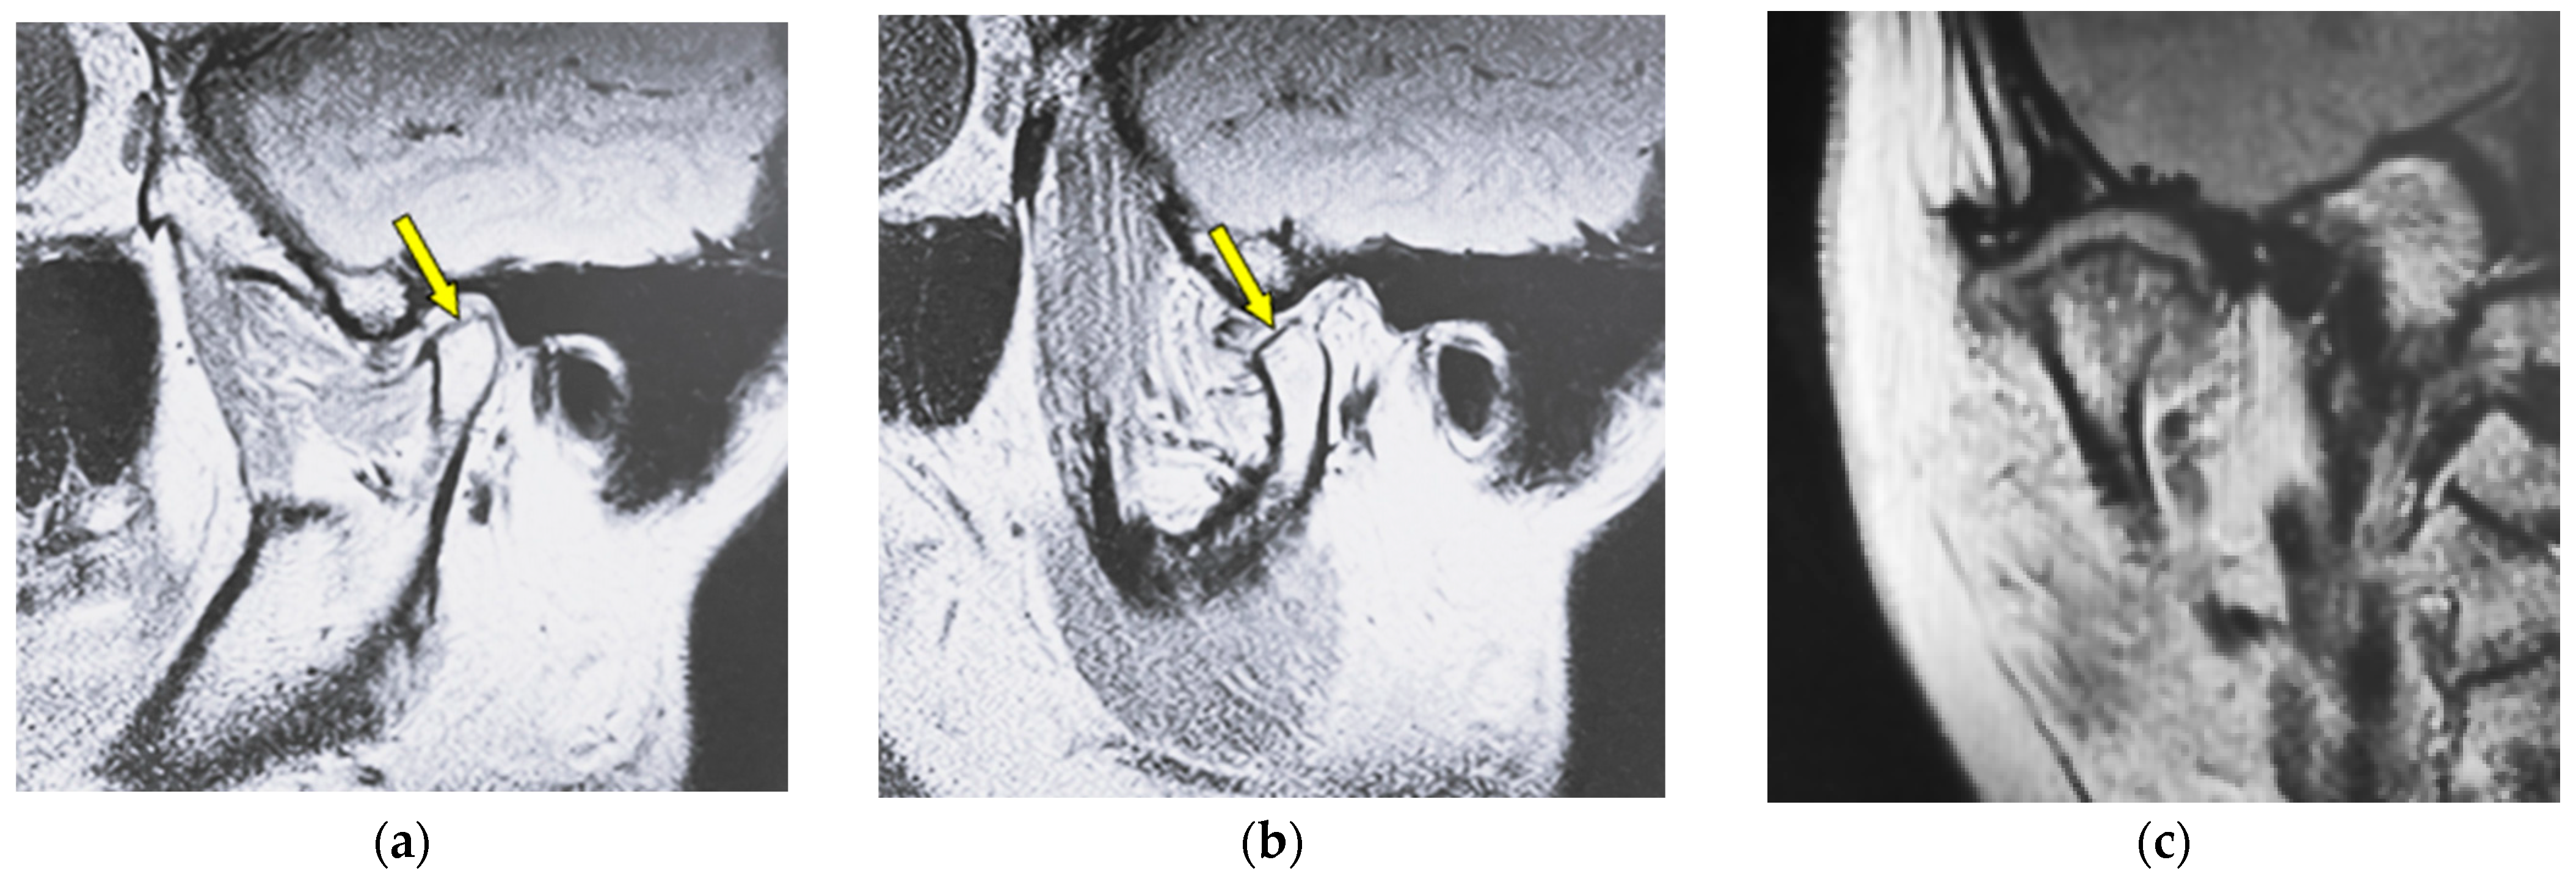

Figure 2 shows MR images of a 51-year-old woman with flattening (right TMJ). Sagittal oblique cross-section imaging (proton-density-weighted) shows anterior disc displacement in the mouth-closing position (Figure 2a) and in the mouth-opening position (Figure 2b).

MR image (proton-density-weighted) of a 51-year-old woman (disc displacement without reduction, right disc): (a) sagittal oblique cross-section imaging in the mouth-closing position; (b) sagittal oblique cross-section imaging in the mouth-opening position; (c) coronal oblique cross-section imaging in the mouth-closing position. The arrow shows the part with flattening.